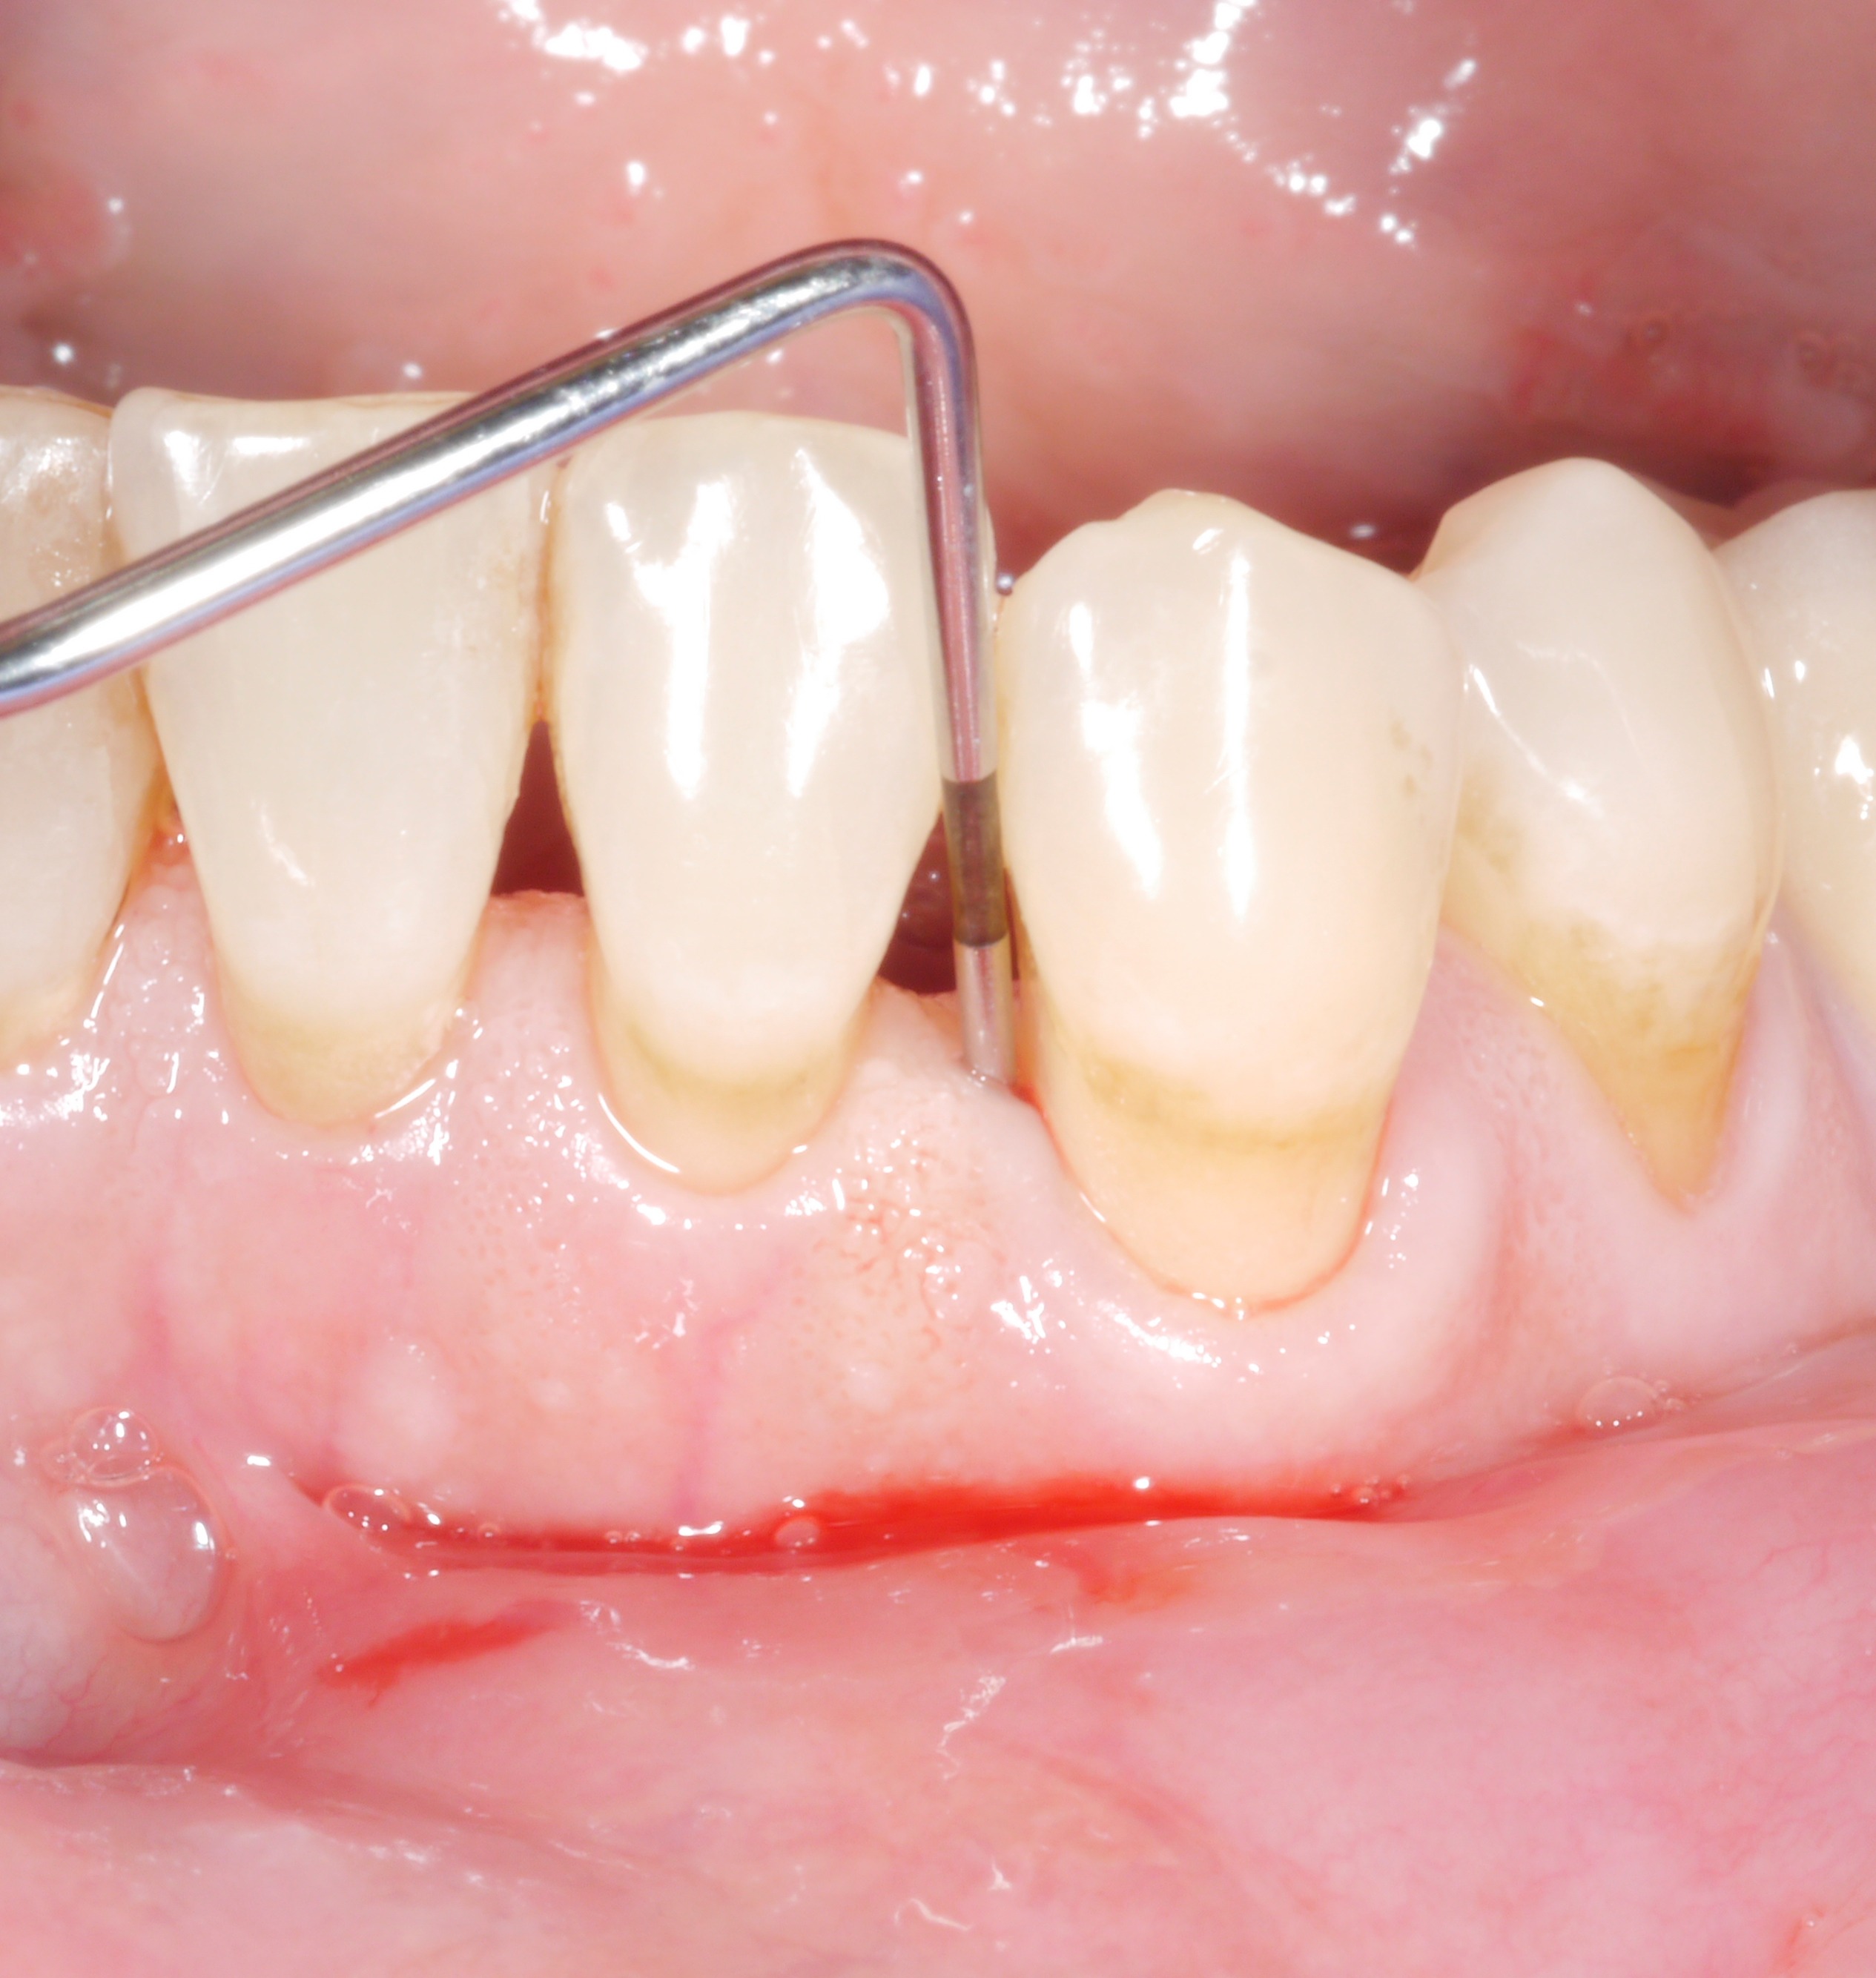

Toutefois, les dentistes ne devraient pas se contenter de profondeurs de sondage résiduelles. En effet, même des profondeurs de sondage résiduelles de plus de 4 mm constituent un problème, du moins à long terme, tant pour la dent concernée que pour le reste de la dentition.

• Les saignements au sondage doublent le risque de perte ultérieure de dents.

Conclusion : l'objectif du traitement devrait être d'obtenir des profondeurs de sondage des poches de 4 mm maximum et une absence d'inflammation !